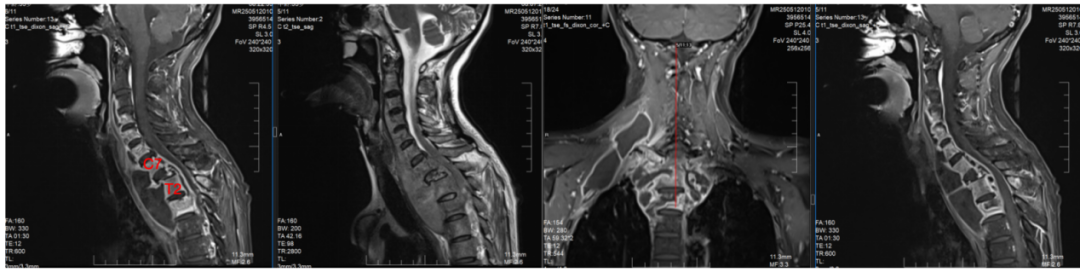

危急时刻,在朋友的建议下,艾女士辗转来到长沙市第一医院脊柱外科。入院检查结果令人揪心:8个椎体不同程度被掏空,最严重的胸1椎体被细菌啃掉90%(图1)、颈部巨大脓肿并流到椎管内压迫脊髓导致双下肢瘫痪(图2),肩部也有巨大的脓包(图2)、重度贫血、严重营养不良。若艾女士的病情无法及时控制,必将危及生命。

图2多学科协助+手术助患者获得新生

为挽救患者神经功能,抢救患者生命,向伟能迅速组织多学科会诊,为患者量身定制个性化治疗方案:标准四联抗结核治疗、急诊一期颈椎前后路联合病灶清除植骨内固定手术。经过紧急而周密的准备,向伟能团队为艾女士实施了颈椎后路病灶清除椎管减压融合内固定术和颈椎前路病灶清除植骨融合术(图3)。历时6小时,手术团队成功将“蛀骨”病灶一网打尽,并用自体骨填补骨缺损,筑牢脊柱“支撑系统”。得益于成熟的MDT围手术期管理模式,该患者在6小时内顺利完成涵盖9个椎体的融合手术,以及后路联合前路的颈椎病灶清除术,术后患者情况稳定,直接被送返至普通病房,无需转入ICU监护。

术后第一天,艾女士的双下肢活动能力便明显改善,颈部疼痛大幅缓解。在医护团队的精心照护下,通过高蛋白饮食调理、早期康复训练及精准用药,术后复查MRI显示脓肿基本清除(图4),患者双下肢肌力恢复4级。术后10天患者顺利出院。家属紧握医生的手感慨地说:“是你们的团队给了她重新站起来的机会!”

图4术后3月患者可在辅助下行走,未来康复的路还很漫长,衷心祝愿她能再一次用自己的脚步去丈量这个美丽的世界。